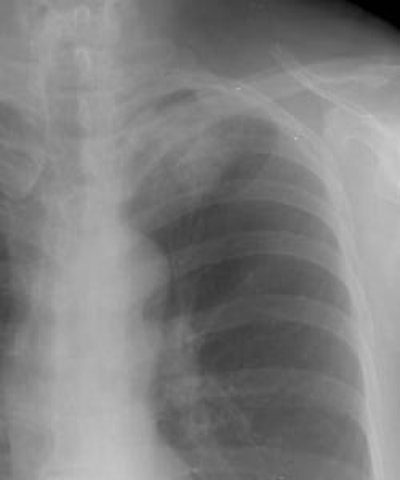

Example 2: This patient had a large peripheral squamous cell carcinoma that had a long area of contact with the chest wall on CT (Click here to view the patients CT scan). Following percutaneous biopsy of the mass the patient developed a large left pneumothorax. Although the left upper lobe collapsed, it did not completely fall away from the chest wall (blue arrow) increasing the concern for chest wall invasion in this case. At surgery, visceral pleural invasion was found, but there were only fibrous adhesions between the visceral pleura and the chest wall. There was no parietal pleura or chest wall invasion. Benign pleural adhesions are a cause of false-positive results when assessing for chest wall invasion with iatrogenic pneumothorax.